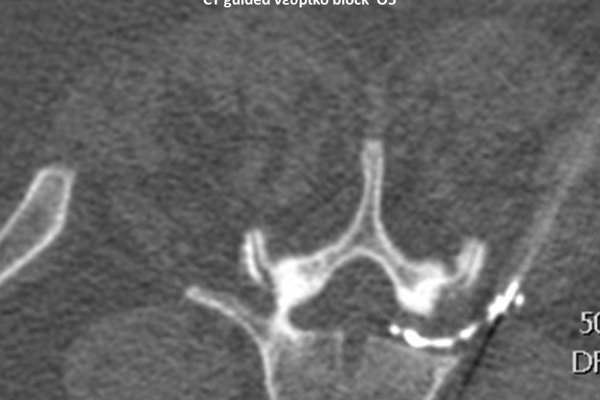

Με την βοήθεια της επεμβατικής ακτινολογίας είναι δυνατόν να πραγματοποιηθούν διαφορες ενέσιμες τεχνικές που αποσκοπούν στη μείωση του μυοσκελετικού πόνου, την ενίσχυση της αποτελεσματικότητας της φυσιοθεραπείας και την επιτάχυνση της διαδικασίας επούλωσης. Οι τεχνικές αυτές περιλαμβάνουν την κατευθυνόμενη έγχυση φαρμάκων ή πραγματοποίηση θεραπευτικών χειρισμών ακριβώς στη θέση τηςπαθολογία. Ετσι εξασφαλιζεται η μέγιστη αποτελεσματικότητα ( έως 95% κατά περίπτωση) και ασφάλεια σε σχέση με τυφλούς χειρισμούς χωρίς ακτινολογική καθοδήγηση.